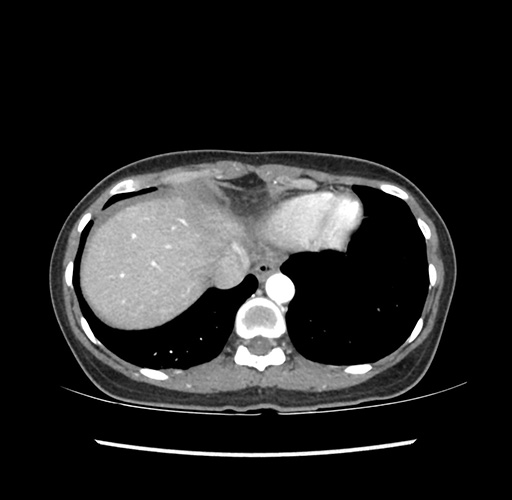

Imaging Analysis

Look through the patient's CT scan to identify any areas of concern for the necessary procedure.

Based on your CT findings, which issue(s) would give reason for "planned slowing down moment(s)" in this case?

Considering a standard left lateral sectionectomy procedure, what step(s) of the operation would you do differently in this case ?